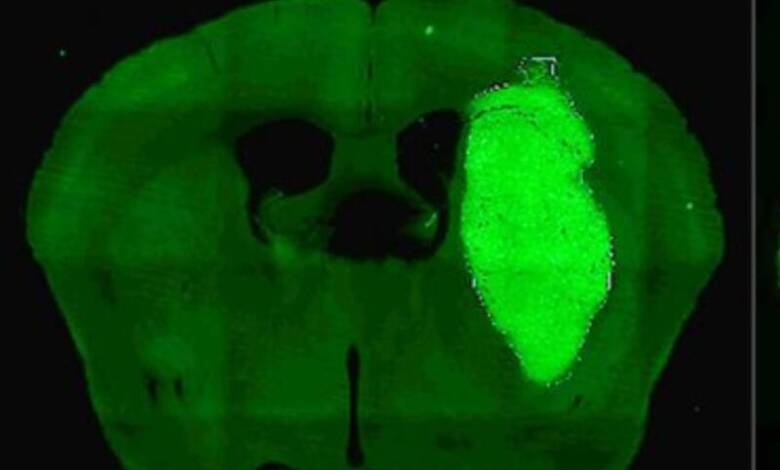

Un avance prometedor surge desde el CONICET para enfrentar el glioblastoma, el tumor cerebral maligno más común y resistente en adultos, conocido por su rápido crecimiento y escaso pronóstico. Los investigadores argentinos lograron frenar el desarrollo de esta enfermedad en modelos preclínicos mediante una estrategia terapéutica que potencia la respuesta a la quimioterapia y la radioterapia, tratamientos tradicionales que hasta ahora tienen resultados limitados.

La clave de esta innovación radica en el bloqueo de la proteína Foxp3, que se expresa en las células del glioblastoma y contribuye a la resistencia del tumor. Mediante una molécula llamada P60, que inhibe Foxp3, los científicos detectan una reducción significativa en la viabilidad y migración de las células cancerosas, así como en la proliferación de vasos sanguíneos que alimentan el tumor. Los experimentos incluyen modelos celulares humanos derivados de biopsias y ratones con tumores cerebrales, donde la terapia combinada logró erradicar el cáncer en un porcentaje significativo de casos.

El laboratorio liderado por Marianela Candolfi, investigadora principal en el Instituto de Investigaciones Biomédicas (INBIOMED), confirmó que la administración de P60 a través de un vector adenoviral dentro del tumor permite una expresión localizada y sostenida, lo que mejora el tratamiento y minimiza los efectos secundarios. “No observamos toxicidad neurológica, lo que sugiere un buen perfil de seguridad para futuras aplicaciones clínicas”, afirmó Candolfi.